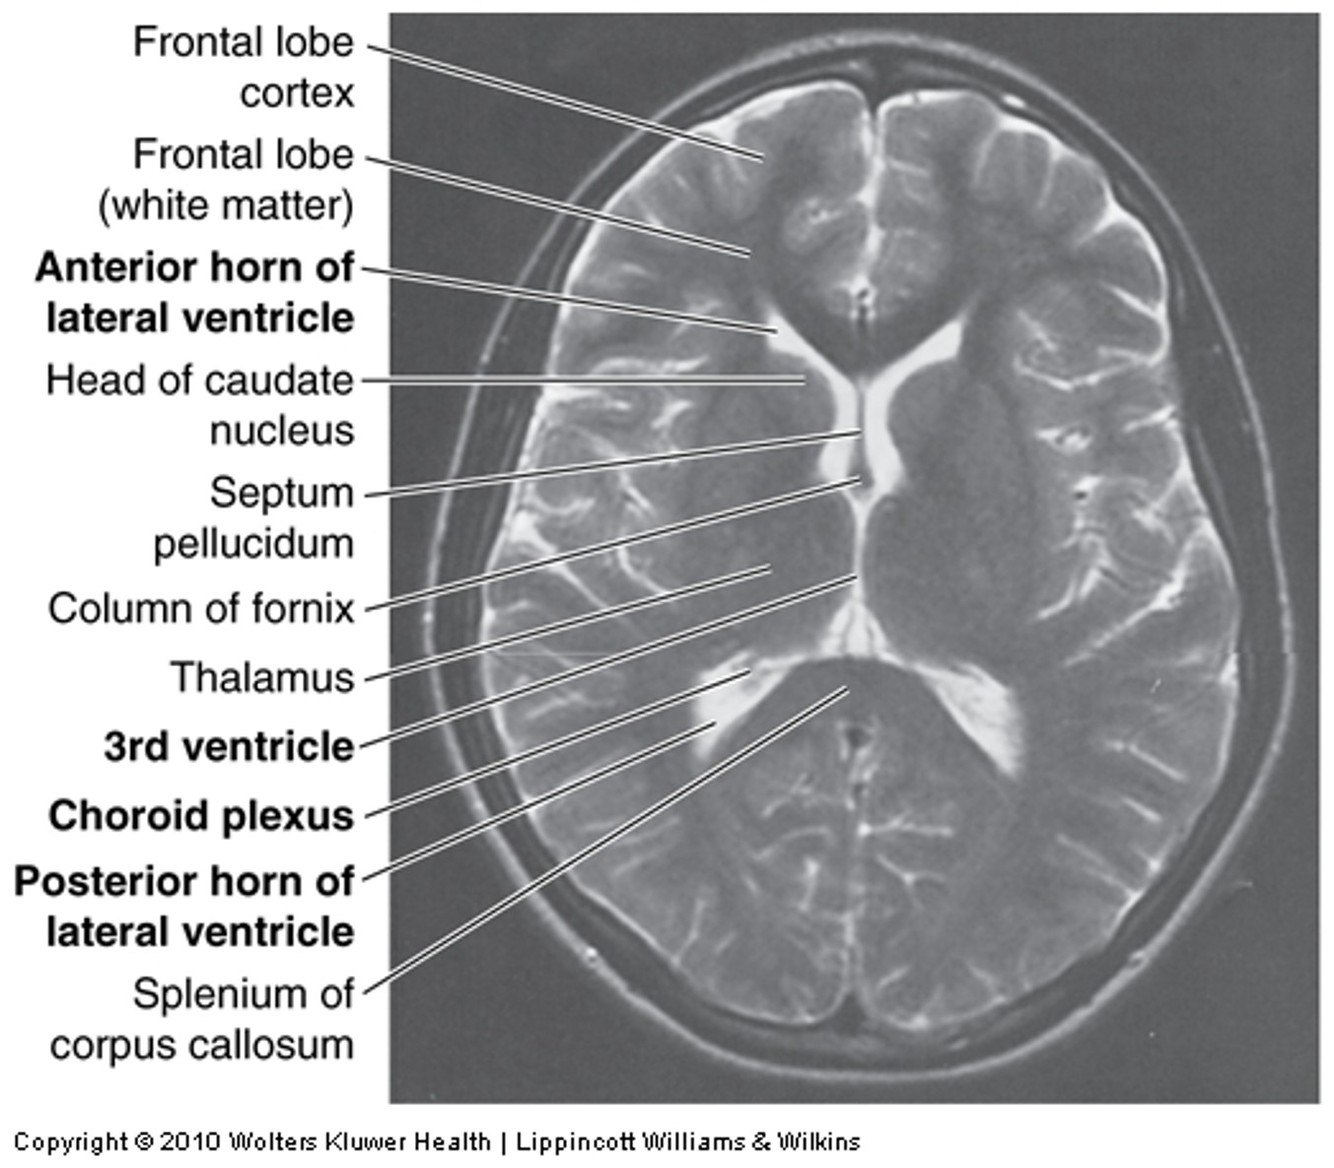

Ventricular system

ECF in brain: like blood but less protein & diff [ion]

formed by choroid plexus in 4 ventricles of brain

absorbed via arachnoid granulations (villi) into venous blood in dural venous sinuses

approx 400 mL/day CSF –> venous circ